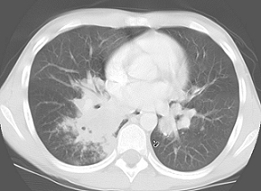

Due to the characteristic cavitary lesion on chest radiographs, suspicion for Staphylococcus aureus pneumonia was high; hence, treatment with an intravenous (IV) vancomycin and IV cephalosporin was initiated. Several days of antimicrobial therapy resulted in no clinical improvement. A computed tomography (CT) scan of the thorax showed a large cavitary air-space opacity in the right lung and perihilar region, areas of necrosis and cavitation, and dense consolidation in right lower lung.

Figures 2a and 2b. Thoracic CT scans showed a large air-space opacity and areas of necrosis and consolidation.